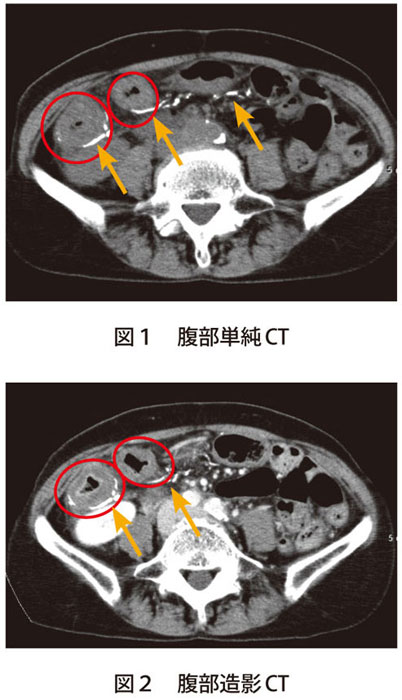

解答 解説 慢性的な腹痛です 原因を発見してください 実践 画像診断q A 羊土社 レジデントノート 実践 画像診断q A 羊土社 レジデントノート 羊土社